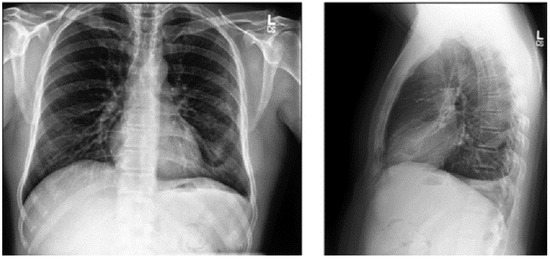

The dataset comprises 112,120 X-ray images with disease labels from 30,805 unique patients [21]. The samples from the CXR NIH dataset are shown in Figure 3. Disease labels were extracted from radiology reports using NLP, achieving over 90% accuracy and supporting weakly supervised learning.

Figure 3.

CXR NIH dataset samples [21].

In order to gain a representative insight into the subject matter, the study utilized the CXR NIH dataset. This is a large-scale hospital-grade database comprising 108,948 frontal-view CXR images from 32,717 patients, and it has gained recognition as a valuable resource within the field [22]. The dataset includes images labeled for eight common thoracic diseases using an NLP system applied to radiology reports. While this automated approach enables scalable and consistent labeling with over 90% estimated accuracy, it may occasionally produce ambiguous or incorrect labels.